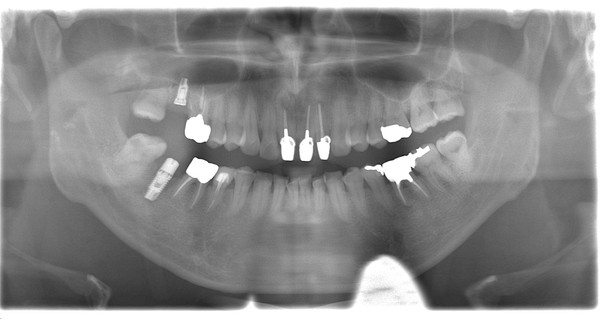

右の上奥歯に1本と右下奥歯に1本の計2本のインプラントオペでした。

上顎の奥歯は、骨の厚みが不足しており、ソケットリフトと呼ばれる骨を足す処置を同時に行いました。

予定通りの位置にしっかりインプラントを処置できたかと思います。